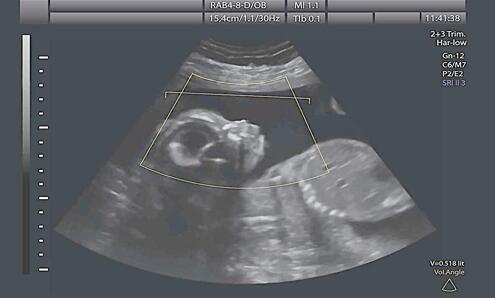

小小的胎儿在妈妈肚子里打着哈欠,当这个画面出现在彩超屏幕上时,28岁的秦女士激动不已。和秦女士一样,想看看腹中孩子的家长有不少,还有一些家长想提前知道孩子的性别,于是胎儿摄影越来越火。近日,记者走访发现,南京有多家胎儿摄影中心,除了拍照,他们还会通过送小礼物来暗示胎儿性别。(据 2月21日《现代快报》)

事实上,一些公司以“胎儿摄影”名义为孕妇提供四维彩超服务,确实是为非法鉴定胎儿性别提供了可乘之机。比如,一些经营者自作聪明,通过送小礼物来暗示胎儿性别,如此虽不明说,但也和告知胎儿性别无异。倘若店内B超机操作者的专业性不强,甚至缺乏相应的资质,更有可能带来巨大的巨大的安全隐患。

三则应做好相关知识的普及。上述《通知》就提出,加大科普宣传和法治教育,正确认识四维超声检查技术的效果和不确定性。而据了解,四维彩超的原理和普通超声并无两样,但是为了加快成像速度,探头上声波线的数量被大幅度增加了。并且,超声仪必须由受训的专业人士操作等。这就需要通过舆论宣传,引导公众科学理智选用“胎儿摄影”。